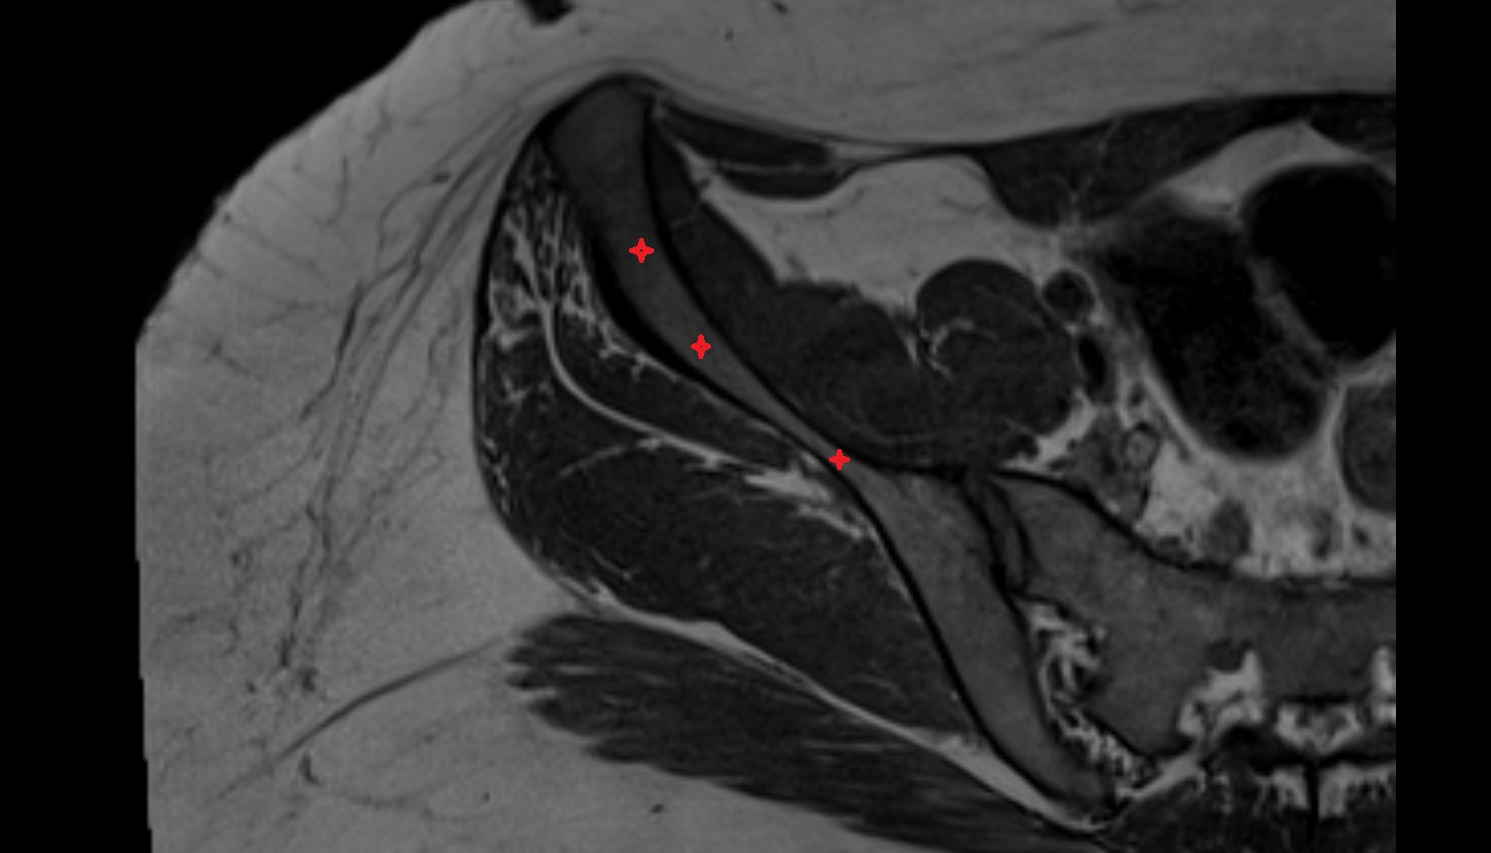

- Corpus cavernosum

- Corpus spongiosum

- Bulb of Penis

- Crus of penis